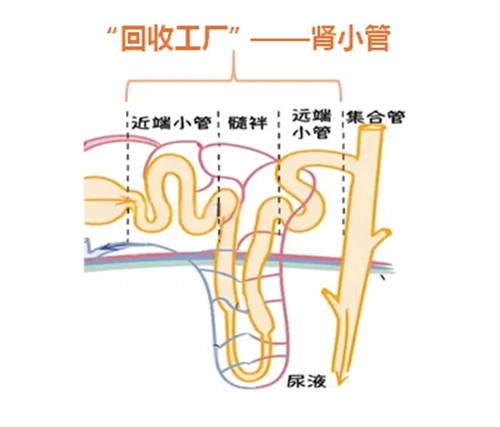

肾小管作为“回收工厂”,

它会选择性的对原尿中有用的物质

进行“回收”。

所以原尿中全部的葡萄糖、小分子蛋白质、大部分水和一部分无机盐可以被肾小管重吸收再次回到血液中循环利用,而剩下的水、无机盐和尿素等就形成了最终的尿液,通过尿道排出体外。

如果肾小管的“回收”能力下降,或者小分子蛋白在血液中产生过多超出了肾小管的回收阈值,就会导致小分子蛋白不能被完全“回收”到血液中,最终在尿液中出现。

所以尿液中如果以小分子蛋白为主时,一般考虑肾小管病变。